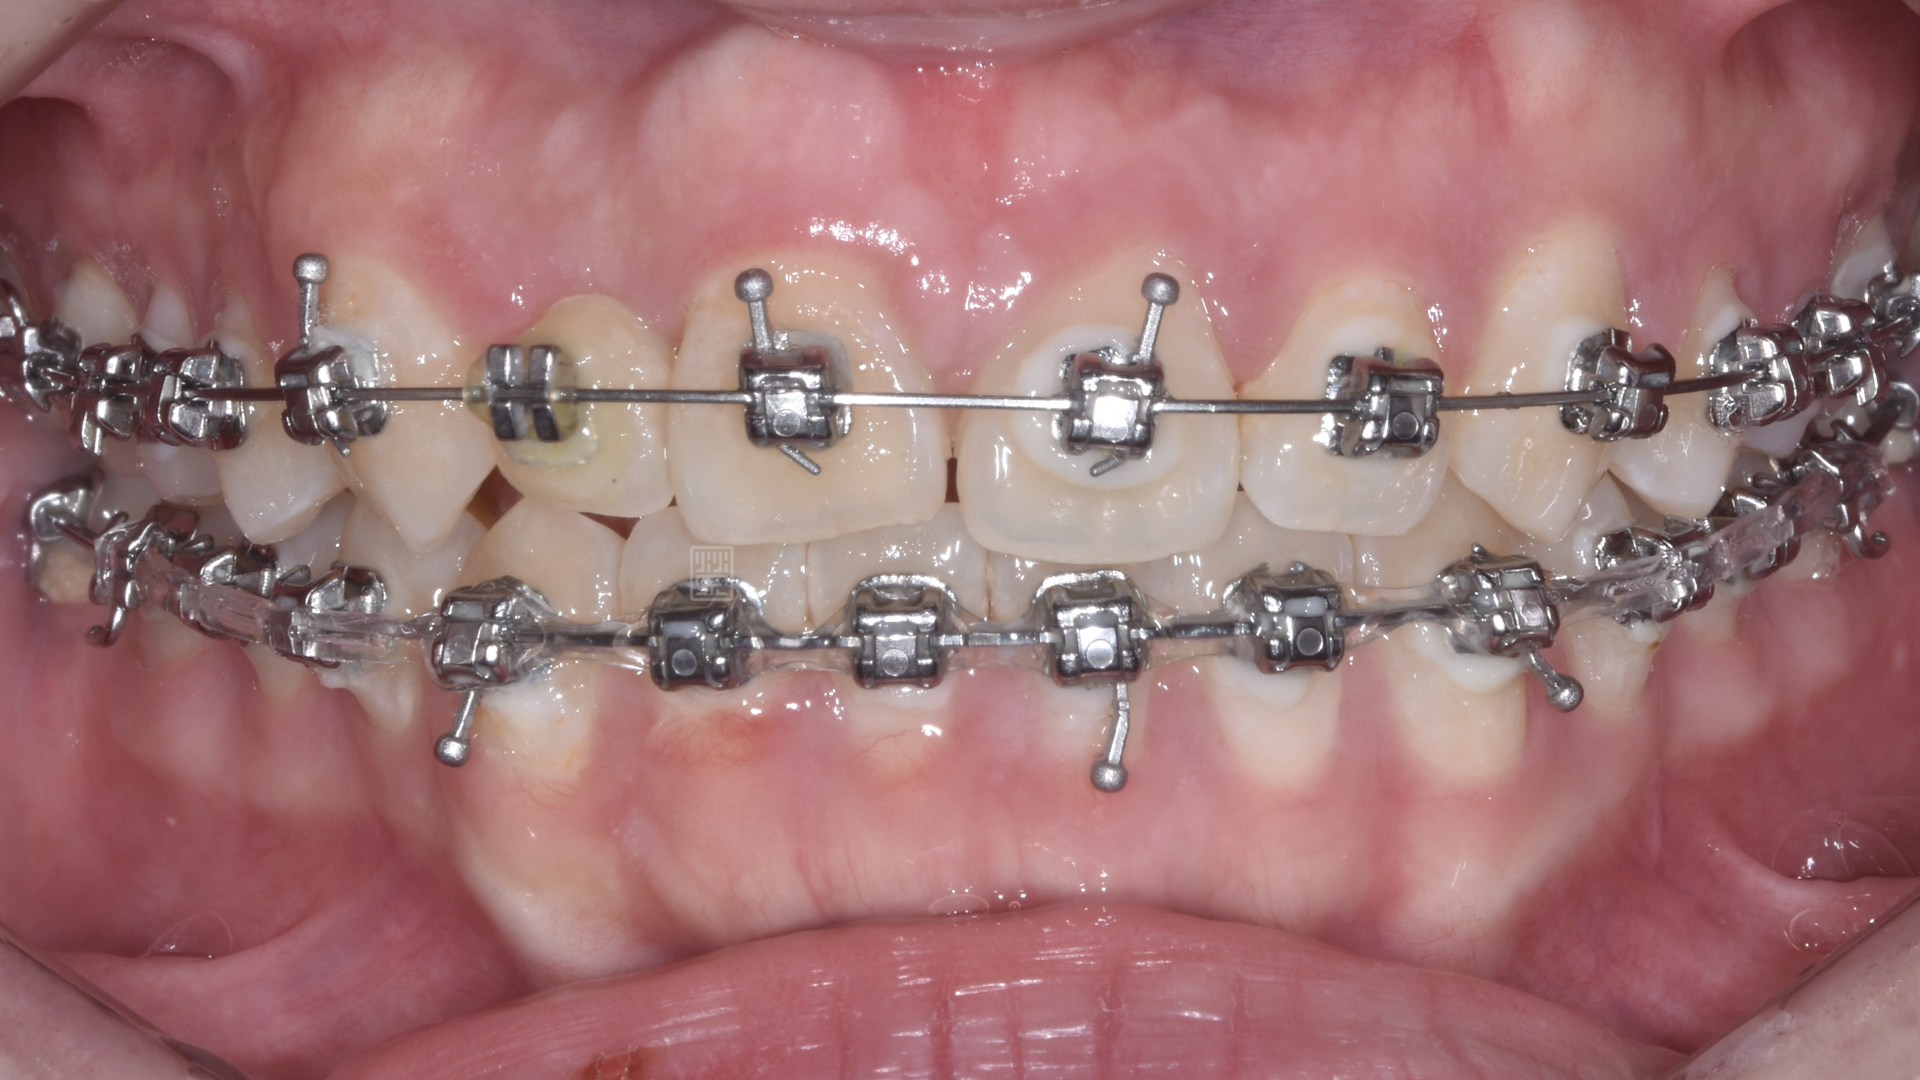

矯正移出側門牙空間

首先張馨文醫師先將牙齒重新排列,但是在門牙的部分因為先前外傷關係,牙齒發生沾黏的狀況,牙齒移動度很小,吳禕凡醫師藉由皮質骨手術加上術後立即施力,將門牙拉至中央位置,並且給側門牙植牙適當空間。

由於門牙本身偏短,藉由微笑分析,決定由牙冠增長術與改變牙齒長度讓門牙達到更好的比例與對稱性,加上側門牙植牙牙齦的調整,並且將右側犬齒用全瓷冠恢復犬齒導引,達到保護性咬合,對未來咬合性穩定性更有幫助。